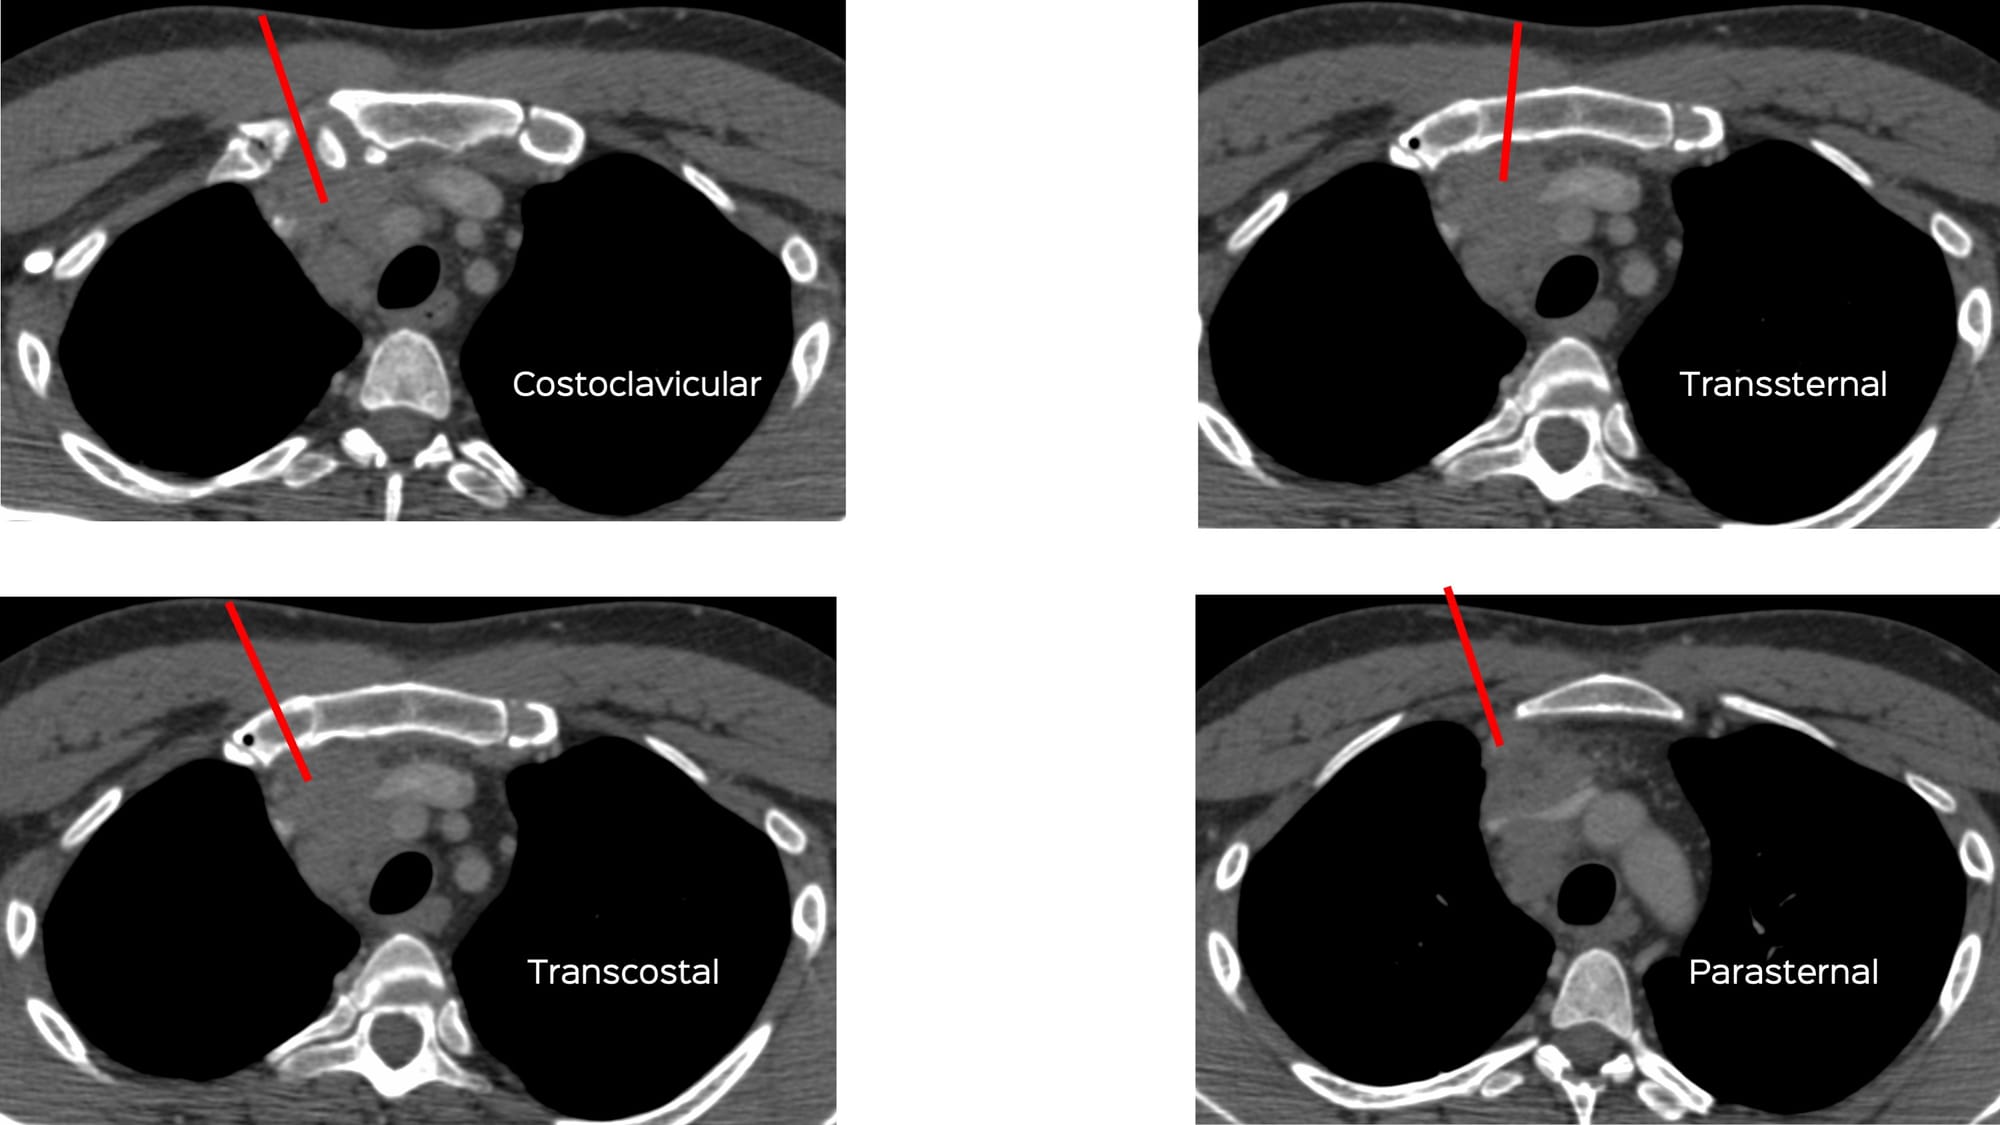

A 46-years old presented with a prevascular space nodal mass extending into the middle mediastinum.

A biopsy was asked for.

What route will you take?